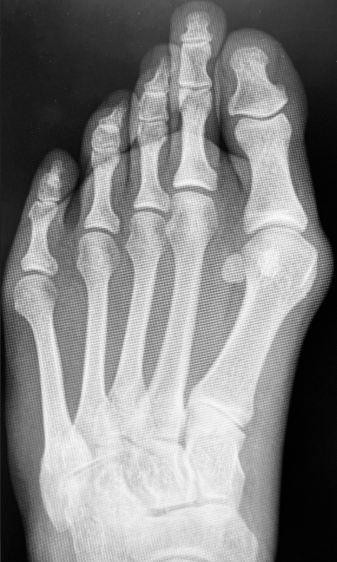

The Weil osteotomy remains the most widely used technique for surgical management of metatarsalgia and is often considered the procedure of choice for this condition. Dr. Lowell Weil, DPM, FACFAS, described an osteotomy oriented parallel to the weight-bearing surface of the metatarsal, which allows controlled proximal translation of the capital fragment to achieve axial decompression.1 Surgeons can perform the procedure with or without fixation and with consistent demonstration of favorable outcomes.2

Although reports of floating toe are common as a radiographic consequence of the Weil osteotomy, its clinical significance is often limited, with multiple studies demonstrating that most floating toes are not painful and do not affect patient satisfaction or function.3,4 Nonetheless, high reported incidence rates—Wagner and colleagues noted 57% at ≥4 years5, and Hofstaetter and team reported 68% at 84 months6—have led many surgeons to explore alternative osteotomies, particularly in cases with digital deformity or multiplanar imbalance.

The Weil osteotomy remains particularly effective for metatarsalgia resulting from an elongated lesser metatarsal or “third-rocker metatarsalgia,” a biomechanical concept described by Perry.7 However, in patients with concurrent transverse- or sagittal-plane deformity, alternative osteotomies may better address the underlying mechanics. In our practice, two such options—the dorsal chevron osteotomy and the oblique metatarsal osteotomy—have provided reliable, reproducible correction with no observed cases of symptomatic floating toe.

Dorsal Chevron Osteotomy/Jacoby Osteotomy

The dorsal chevron osteotomy is our preferred technique in patients whose primary pathology is metatarsal parabola disruption, with minimal digital deviation. Its V-shaped geometry provides intrinsic transverse-plane stability, and because the osteotomy takes place in the metatarsal neck, the MTPJ capsule can largely remain intact—limiting soft-tissue morbidity.